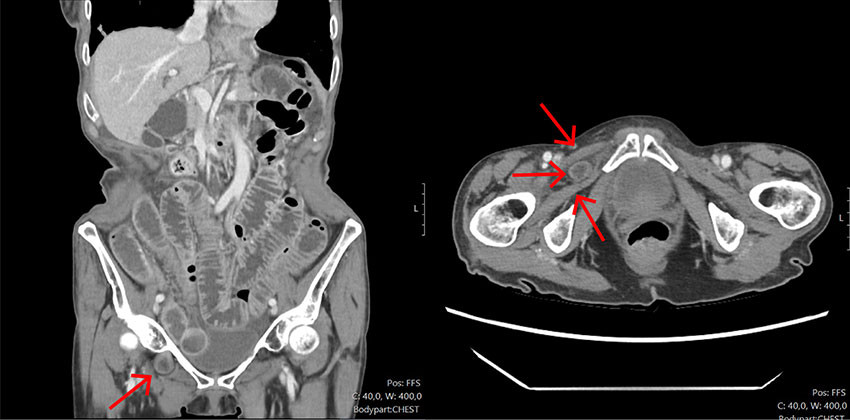

Dag fire ble kvinnen klinisk dårligere med takykardi og puls på 119 slag/min, respirasjonsfrekvens på 28 per minutt (12–16 per minutt) og feber, temperatur 38,1 °C. Det var samtidig CRP-stigning fra 50 til 250 mg/L. Det ble startet med piperacillin-tazobactam i vektredusert dose, 2 g x 4 intravenøst, og hun ble henvist til CT toraks/abdomen/bekken med mistanke om sepsis fra abdominalt fokus. CT viste inneklemt tynntarm i høyre obturatorkanal og preobstruktiv dilatasjon av tynntarm, forenlig med et akutt irreponibelt obturatorhernie (figur 1a og 1b). Pasienten ble derpå raskt tilsett av vakthavende kirurg og meldt som øyeblikkelig hjelp til operasjon.